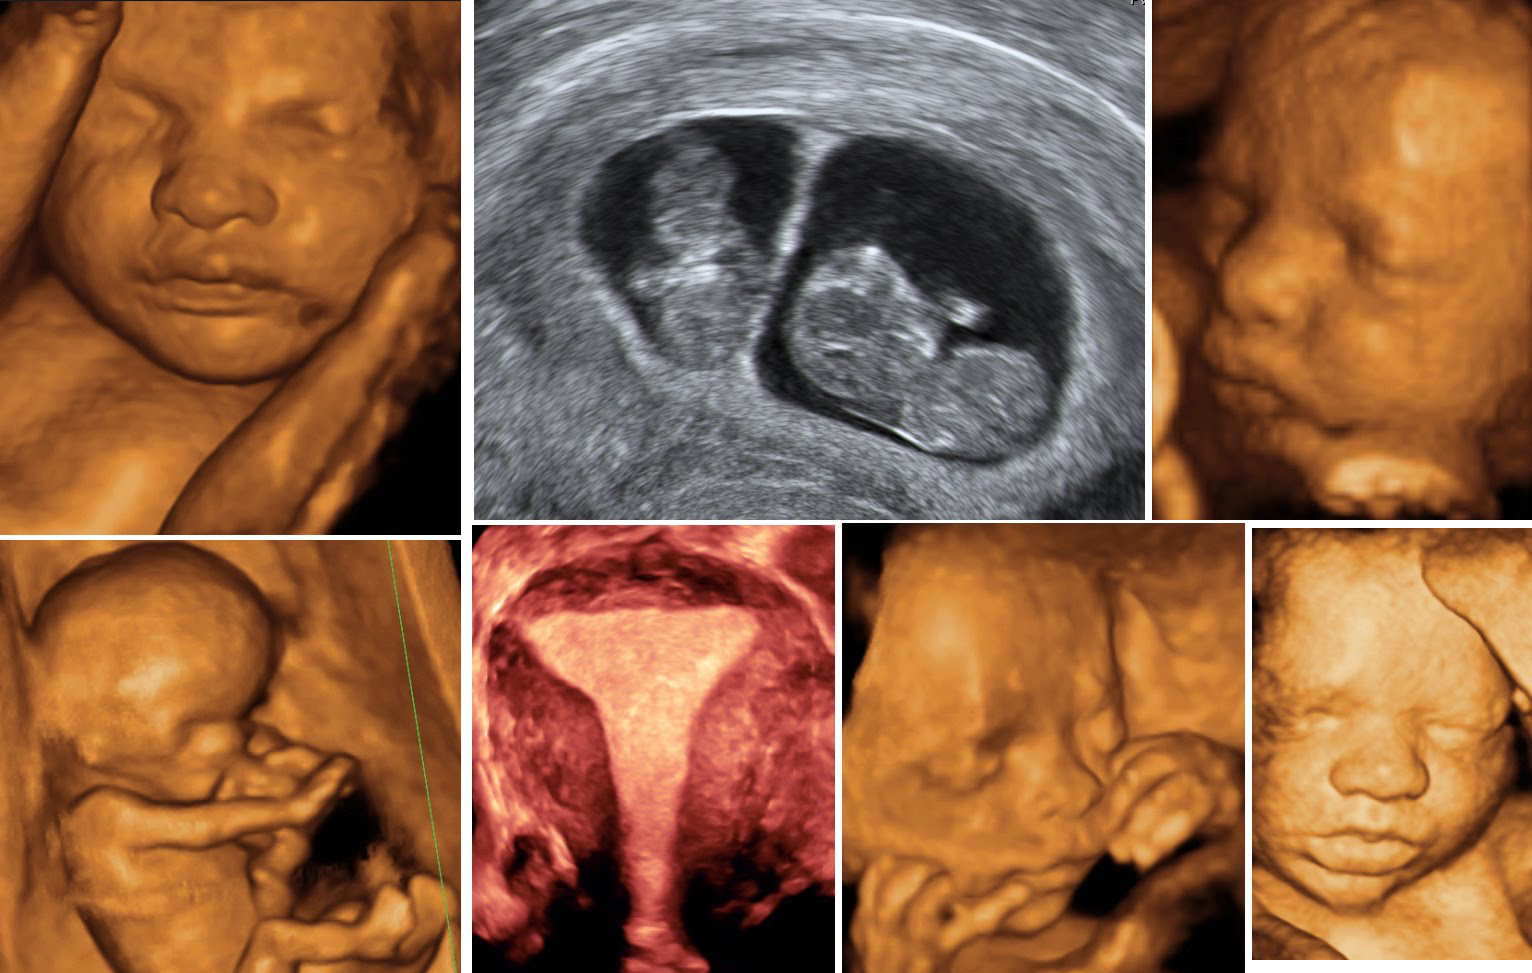

For Anjali, the major problem was emotional—anxiety about her baby's well-being. This is where the Obstetric Color Doppler emerged as a beacon of reassurance. The scan provides real-time images, allowing expectant mothers and their healthcare providers to assess the baby's blood flow and detect any potential issues early on. This peace of mind is invaluable, ensuring that mothers like Anjali can enjoy their pregnancy with a little less worry.

The Obstetric Color Doppler scan is a powerful tool that offers multiple benefits. It not only monitors the health of the baby but also evaluates the placenta's function and the blood flow in the umbilical cord. This detailed information allows doctors to make informed decisions about the pregnancy, ensuring both mother and baby receive the best care possible.